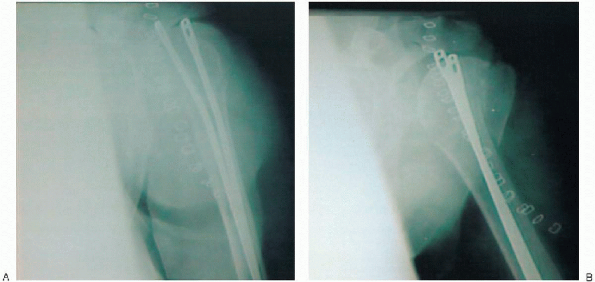

FIGURE 5-19. Intraoperative anteroposterior view of the shoulder with the humerus in internal rotation (A), external rotation (B), and axillary (C).

|

![]() |

FIGURE 5-19. (continued).

This includes an AP view of the shoulder with the humerus in internal

rotation (on the chest) and maximum external rotation as defined by the

intraoperative assessment. An axillary view is also obtained.